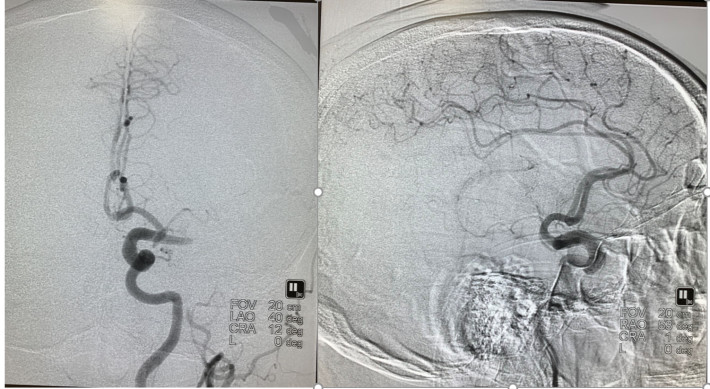

患者发病到入院时间超过4.5h时间,静脉溶栓时间窗超过,考虑大血管病变,患者急诊CT提示左侧大脑中动脉高密度征,ASPECTS评分9分,未见明显低密度灶,结合患者急诊查体,高度提示左侧颈内动脉系统大动脉闭塞。与家属沟通后,急诊行DSA,必要时予血管内治疗。

通过推拉按摩技术后支架打开好转。

术后造影,mTICI分级III。

一、该患者血栓负荷较重,得益于加奇申翼®取栓器独特的前段“网兜”设计,经历2次取栓,但无明显血栓逃逸。此外,该产品还具有较长的工作长度和更大的网孔设计,良好的血栓嵌合能力以及优秀的抗折性和贴壁性,支架可以整体显影,并可以在内腔为0.017 inch的微导管输送。

二、对于支架与血栓嵌合处可能出现支架打开欠佳,通过推挤、按摩支架可使支架打开良好,增加对血栓的切割力,提高取栓成功率。